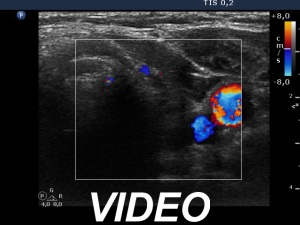

Ultrasonography. The pattern was essentially the same. The only difference concerned the lesion in the dorsal part of the right lobe which clearly increased in size. Moreover, it became more obvious that the lesion had microcalcifications.

Suggestion: In agreement with the referring physician, surgery was proposed because there was a suspicion of thyroid cancer despite the negative cytology.

Histopathology disclosed Warthin-like variant of papillary cancer. and Hashimoto's thyroiditis.

The discrete lesion showed see features on which a different pathology could be suspected: in contrast with other hypoechoic smaller areas, the larger lesion was more hypoechoic, had a more regular shape and had microcalcification.

Considering above described circumstances and the significant increase in size, it seemed to be rational to suggest surgery.